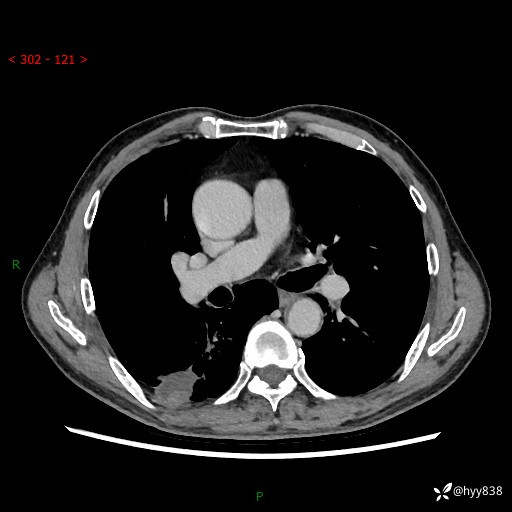

辅助检查:CT

胸部CT平扫

增强